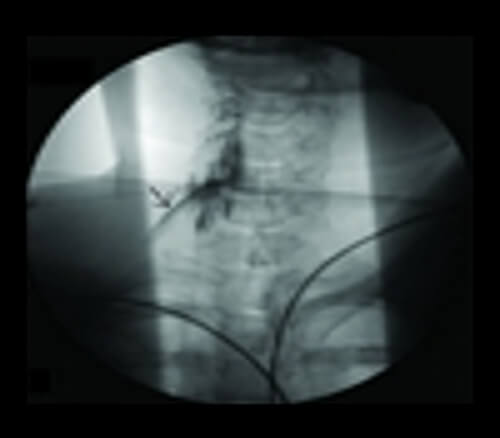

Risk of Extravasation

IV infiltration is one of the most common problems that can occur when fluid infuses into the tissues surrounding the venipuncture site. This sometimes happens when the tip of the catheter slips out of the vein, the catheter passes through the wall of the vein, or the blood vessel wall allows part of the fluid to infuse into the surrounding tissue.

Extravasation occurs when there is accidental infiltration of a vesicant that can cause blistering or chemotherapeutic drugs into the surrounding IV site. Vesicants can cause tissue destruction and/or blistering. Irritants can result in pain at the IV site and along the vein and may or may not cause inflammation. Extravasation can result in tissue sloughing, pain, loss of mobility in the extremity and infection.

The extravasation of contrast agents is an unwanted occurrence that can cause irreversible local injuries.

Extravasation of CT scan contrast media into upper extremity subcutaneous tissue is a relatively frequent complication of injection. Contrast extravasation one hour after injection showing a large area in the biceps compartment. Elevation and massage can help with the pain as well as warm compresses.